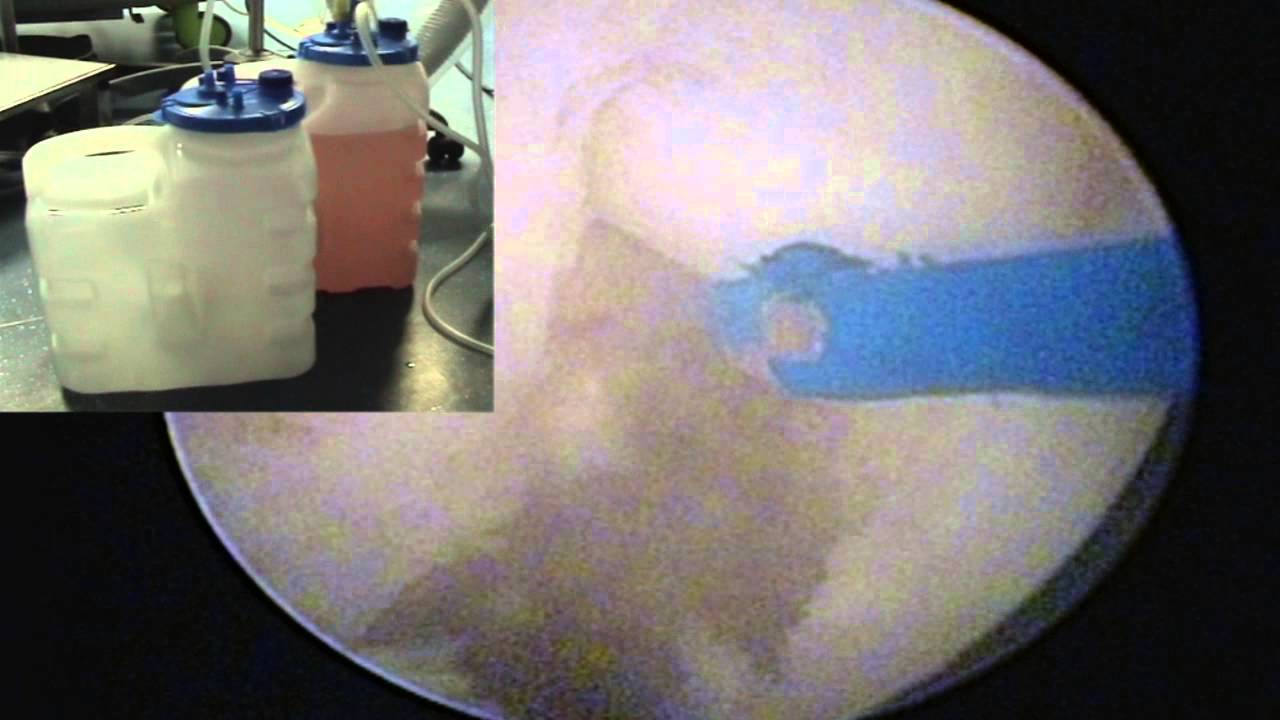

Actualités Enucléation laser de la prostate HOLEP - Symposium Urologique d'Aquitaine 2013